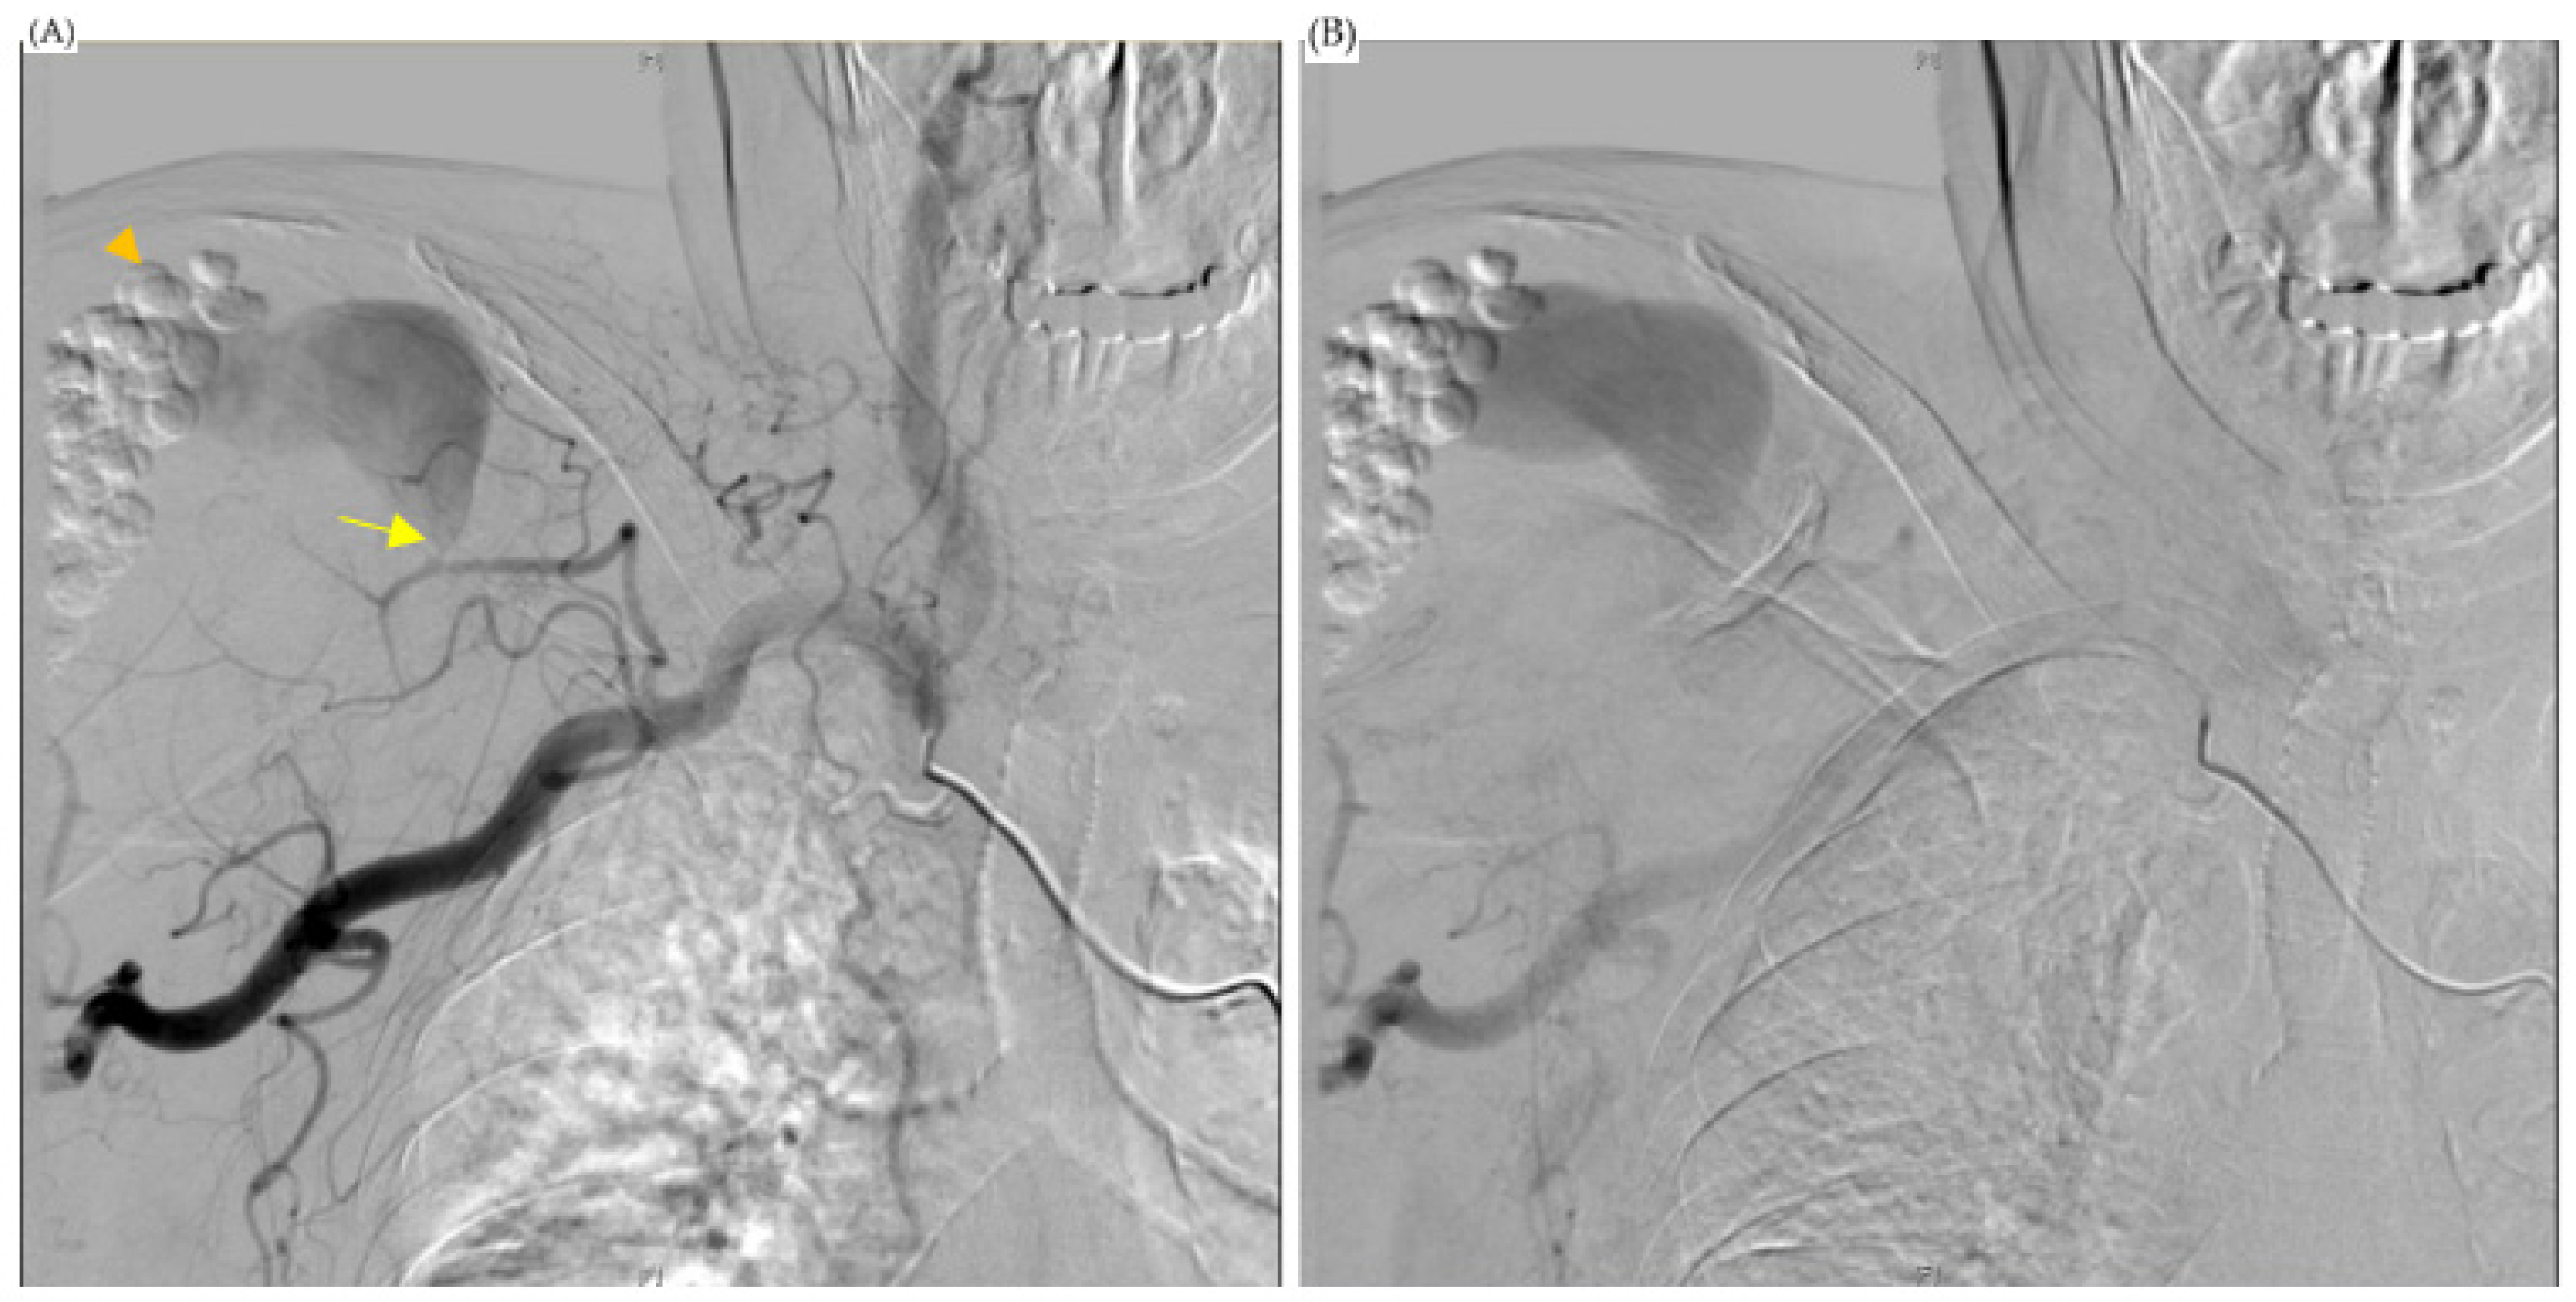

Figure 1.

MRI of shoulder. (A,B) were coronary plane, (C,D) were sagittal plane. All the images showed: 1. An encapsulated cystic mass extending across subacromial and subdeltoid space (arrowhead), which was suggestive of abscess. 2. Enhancing nodule within the supraspinatus muscle, which was suggestive of inflammatory pseudotumor (arrow).